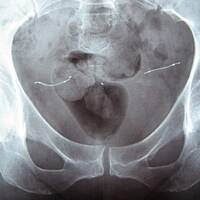

Tout au long de notre enquête sur les implants contracepteifs Essure, nous avons rencontré des femmes à qui on a posé puis retiré ces petits ressorts commercialisés par Bayer jusqu'en 2017. Rozenn Le Carboulec leur a tendu son micro afin de recueillir leurs témoignages saisissants.